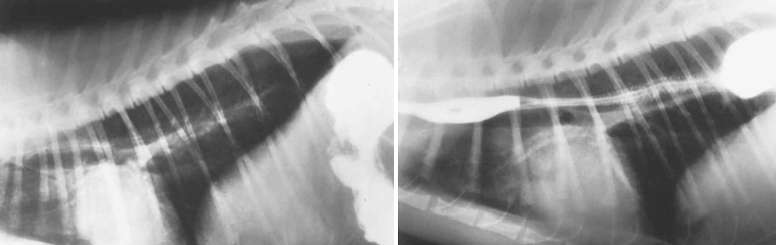

- Positive-contrast esophagography

- Sliding type - 복압에 따라 흉강으로 나왔다 복강에 들어갔다 왔다갔다 할 수 있음.

- 복강을 누르면 확실하게 흉강으로 빠져나오지만, 조영제(barium)가 오연되기 쉬워서 조심해야.

| Plain | Contrast (*Sliding) |